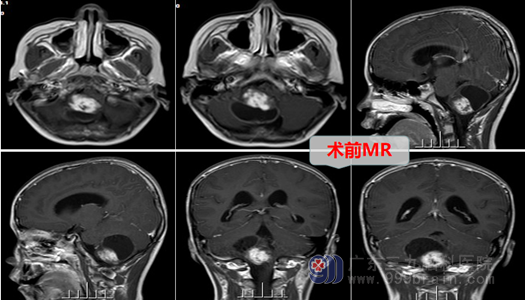

看着病倒在床上的儿子,踌躇了许久,小辉父母商量后,决定直面困境。神经外十科手术团队仔细查看患者影像检查,经过术前讨论,制定了慎密的手术方案,在全麻下行右侧后颅窝开颅行小脑肿瘤切除术。手术过程顺利,一举两得:医生不仅切除了肿瘤,又没有影响到患儿的正常功能,肿瘤病理结果为低级别胶质瘤。